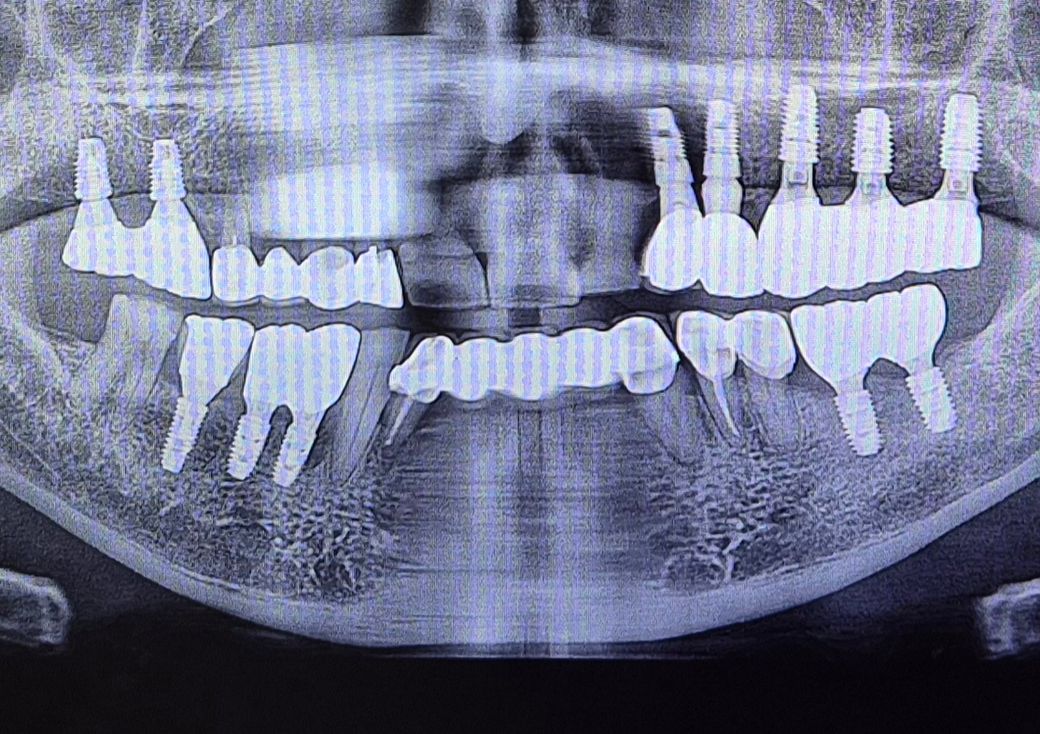

어금니 쪽 한번 봐주실 수 있나요? 임플란트 해야될지..

병원에서 사진을 찍었는데 크라운을 하자고 하셨거든요.

다른 병원 두군데 정도 가보니 임플란트해야된다구. 어금니 밑에가 충치가 있는데 다 썪었다고 크라운으로 해봤자 계속 아플거라고 하시는데

그래서 사진 첨부해봅니다. 이걸로 알 수는 없겠지만.. 저보다는 더 많은 걸 아실테니 한번 올려봅니다.

해당 부분을 크라운 치료를 해도 예후가 좋지 않을 가능성은 높아 보입니다. 즉 추후에 임플란트 등으로 넘어갈 가능성이 커 보입니다. 다만 시간이 걸리더라도 자연치를 살려서 쓸 방법이 있다면 우선적으로 살려서 크라운을 해보고 그래도 증상이 호전되지 않거나 문제가 된다면 임플란트로 넘어가는 것이 좋아 보입니다.

사진상으로는 잇몸뼈가 크게 나쁘진 않은거 같으니 최대한 사용할때까지 사용하시고 추후에 문제가 생기면 그떄 치료를 하셔도 될것같습니다.

해당 사진 외에 치아만 나오는 사진이 있어야 할 듯 싶습니다. 크라운 내부 뿌리까지 충치가 있으면 임플란트 하시는 게 낫습니다.